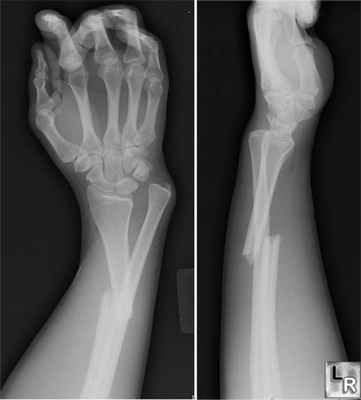

Перелом лучевой кости с вывихом головки локтевой кости (перелом Галеацци) • Причины: падение на вытянутую руку, удары по предплечью • Патоморфология: лучевая кость ломается в нижней трети, её отломки смещаются кпереди (дистальный отломок дополнительно занимает положение пронации из-за сокращения мышц), образуя угол, открытый кзади; головка локтевой кости смещается в ладонную или тыльную сторону • Клиническая картина: характерная деформация (западение на тыльной поверхности предплечья с лучевой стороны и выпячивание на ладонной), искривление оси лучевой кости, пальпируется головка лучевой кости на локтевой стороне лучезапястного сустава, болезненность при пальпации и осевой нагрузке. Надавливание на головку лучевой кости вызывает вправление, при прекращении давления головка снова вывихивается. Необходимо проводить в обязательном порядке рентгенографию с захватом лучезапястного сустава • Лечение: репозиция, гипсовая повязка на 8–10 нед, при неэффективности консервативного лечения — открытая репозиция и остеосинтез лучевой кости, открытое вправление головки локтевой кости.